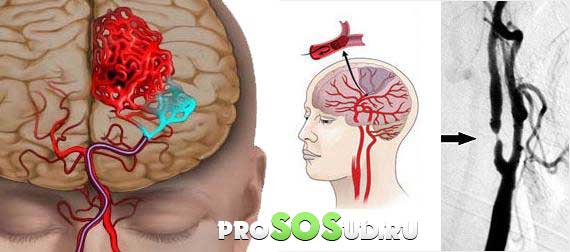

Наихудшим последствием арахноидита является тромбоз или резкая непроходимость в пораженной области, что может привести к серьезным нарушениям кровообращения и ишемии головного мозга.

Ишемия головного мозга.